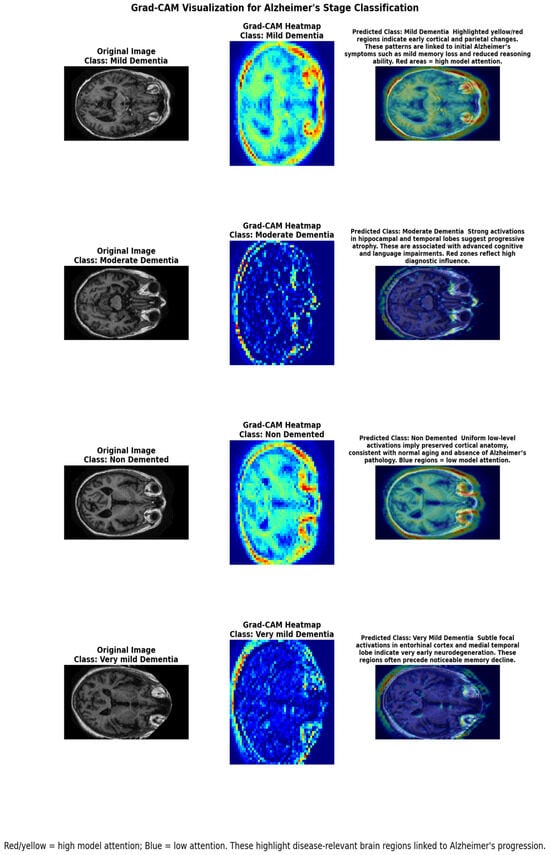

Detection and Classification of Alzheimer’s Disease Using Deep and Machine Learning

by Muhammad Zaeem Khalid, Nida Iqbal, Babar Ali, Jawwad Sami Ur Rahman, Saman Iqbal, Lama Almudaimeegh, Zuhal Y. Hamd and Awadia Gareeballah

Tomography 2026, 12(1), 4; https://doi.org/10.3390/tomography12010004 - 26 Dec 2025

Background/Objectives: Alzheimer’s disease is the leading cause of dementia, marked by progressive cognitive decline and a severe socioeconomic burden. Early and accurate diagnosis is crucial to enhancing patient outcomes, yet traditional clinical and imaging assessments are often limited in sensitivity, particularly at early stages. This study presents a dual-modal framework that integrates symptom-based clinical data with magnetic resonance imaging (MRI) using machine learning (ML) and deep learning (DL) models, enhanced by explainable AI (XAI). Methods: Four ML classifiers—K-Nearest Neighbors (KNN), Support Vector Machine (SVM), Decision Tree (DT), and Random Forest (RF)—were trained on demographic and clinical features. For stage-wise classification, five DL models—CNN, EfficientNetB3, DenseNet-121, ResNet-50, and MobileNetV2—were applied to MRI scans. Interpretability was incorporated through SHAP and Grad-CAM visualizations. Results: Random Forest achieves the highest accuracy of 97% on clinical data, while CNN achieves the best overall performance of 94% in MRI-based staging. SHAP and Grad-CAM were used to find clinically relevant characteristics and brain areas, including hippocampal atrophy and ventricular enlargement. Conclusions: Integrating clinical and imaging data and interpretable AI improves the accuracy and reliability of AD staging. The proposed model offers a valid and clear diagnostic route, which can assist clinicians in making timely diagnoses and adjusting individual treatment. Full article